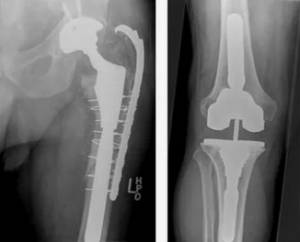

Эндопротезирование коленного сустава было выполнено 64 пациентам (64 сустава), тазобедренного - 42 (42 сустава). Среди больных с эндопротезированием коленного сустава было 13 мужчин и 51 женщина в возрасте от 41 до 79 лет (Ме - 66 лет [Q1 - 62; Q3 - 72]), среди же пациентов с эндопротезированием тазобедренного сустава - 19 мужчин и 23 женщины в возрасте от 39 до 81 года (Ме - 61 лет [Q1 - 55; Q3 - 67]). В обеих группах преобладали женщины, хотя статистический анализ свидетельствует, что по половому признаку (коэффициент %2 = 7,476; р = 0,007) группы несопоставимы. Статистически значимое различие было выявлено и в отношении возрастного признака (критерий Манна - Уитни; р = 0,0008). По величине массы тела группы были однородны (критерий Манна - Уитни; р = 0,301). Анализ половых и возрастных показателей подтверждает то, что остеоартроз крупных суставов чаще встречается у женщин, при этом поражение коленного сустава клинически проявляет себя в более позднем возрасте, чем тазобедренного.

Эндопротезирование коленного сустава преимущественно осуществляли переднемедиальным доступом с обходом надколенника и в половине случаев наложением манжеты на среднюю треть бедра. Тотальное замещение тазобедренного сустава выполняли заднелатеральным или латеральным доступом по Хардингу. Всем больным за 12 ч до операции и через 6 ч после ее завершения водили один из препаратов низкомолекулярного гепарина в соответствии с инструкций. Непосредственно перед операцией внутривенно вводили транексамовую кислоту в дозе 15 мг/кг массы тела, скорость введения составляла 15 мг/мин. Эндопротезирование тазобедренного сустава завершалось «глухим» швом, эндопротезирование коленного - в равной степени «глухим» швом или дренированием раны.